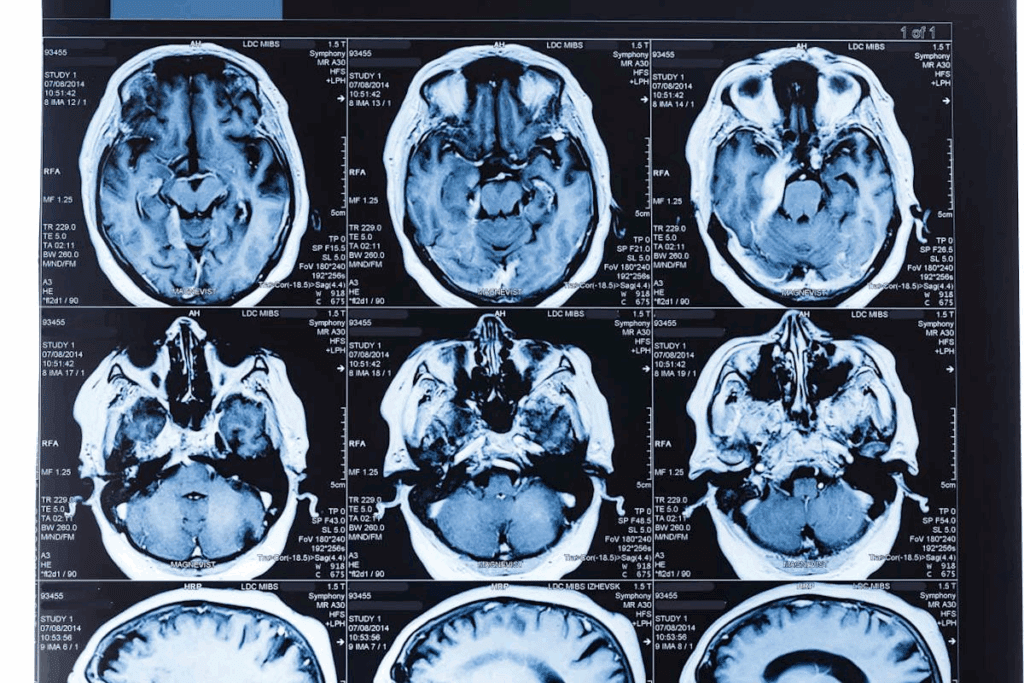

CT Scans for Brain Tumor Detection

CT scans are often used to find brain tumors. It’s key to know what they can and can’t do. They give first clues about a tumor’s presence and type.

How CT Scans Work for Brain Imaging

CT scans use X-rays to make detailed brain images. The patient lies on a table that moves into a machine. This machine takes X-rays from different angles.

These X-rays are turned into images of the brain. Doctors can see any tumors or problems in these images.

What CT Scans Can and Cannot Detect

CT scans are great for finding bleeding, bone issues, and big tumors. They help see tumors that push brain structures out of place. But, they might miss small tumors or those that blend in with the brain.

Can a Brain Tumor Be Missed on a CT Scan?

Yes, some tumors can be missed on a CT scan. This is true for small tumors or those that don’t change the brain’s density much. This is why doctors might use other tests like MRI if they’re unsure.

Radiation Considerations for Pediatric Patients

Using CT scans on kids is a big worry because of radiation. Kids’ bodies are more vulnerable to radiation harm. So, doctors try to use less radiation by adjusting the dose for each child’s size and age.